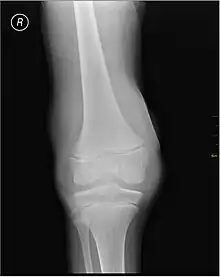

Lipohemarthrosis (blood and fat in the joint space) seen in a person with a subtle tibial plateau fracture. The arrow indicates a fluid level between the upper fat component and the lower blood component.